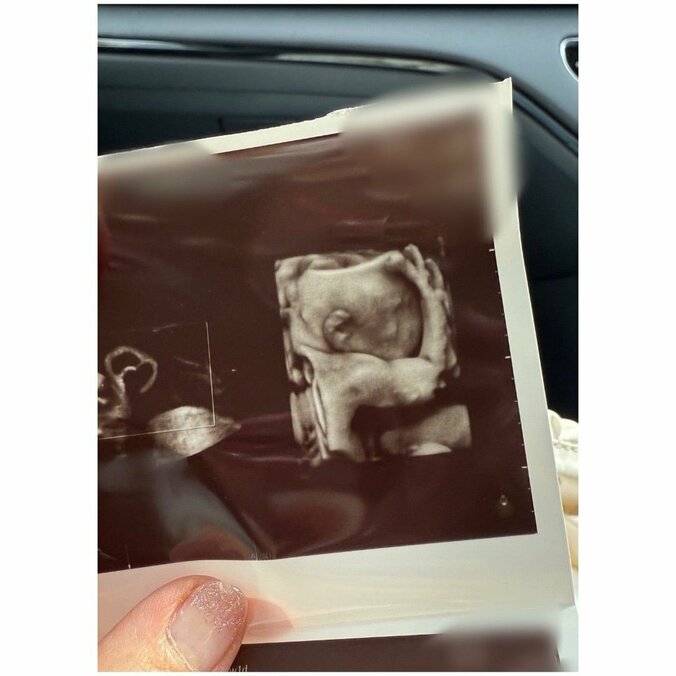

【写真・画像】第5子妊娠中・辻希美、最新エコー写真で驚いたこと「え?本当に?ってなりました」 2枚目 杉浦太陽,辻希美 2025/06/13 12:48 画像2枚目/2枚 【写真・画像】SNS下書き_241218更新 ※※露出系は配信先「nor.」を外すこと!!※※ 2枚目 記事を読む ▼スクロールで次の画像をみる▼ 【映像】辻希美、夫・杉浦太陽と一緒に大鍋で料理 第5子妊娠中の辻󠄀希美(37)、家族で安産祈願へ「おなかぱんぱん」 第5子妊娠中・辻希美、むくみで悩む足の写真を公開 ・「今日は」辻希美オフィシャルブログ 辻希美 人気特集記事 辻希美、長女との仲良しショット&料理姿まとめ 辻希美、お弁当・キャラ弁当&料理・ごはんまとめ 辻希美、自宅・キッチンの様子を公開 まとめ 辻希美、夫・杉浦太陽や家族との仲良しショットまとめ Twitter